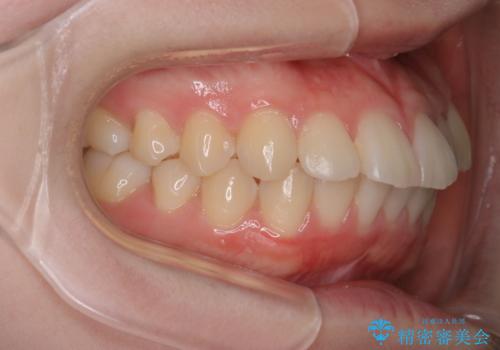

【審美装置】歯を抜いてEラインをきれいに

- 出っ歯を主訴に来院されました。今回は4番の歯を4本抜歯をし、ワイヤー矯正にて治療しました。

抜歯矯正のため2年を予定してましたが、予定よりも早く終わることができました。また口元も下がり、かみ合わせも改善しました。